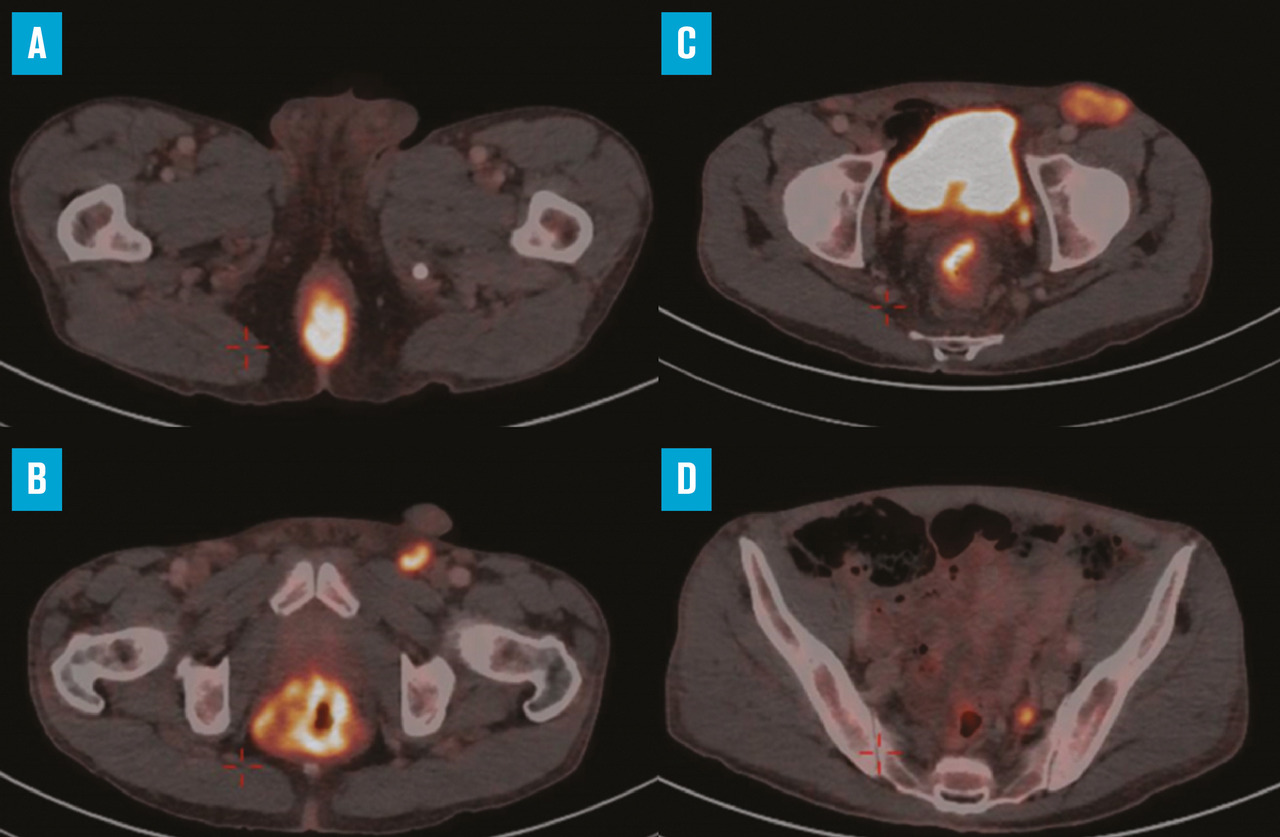

Le 18F-FDG TEP scanner est également recommandé dans le cadre du bilan d’extension du cancer du canal anal. Plusieurs études ont en effet montré son intérêt dans l’évaluation initiale, notamment ganglionnaire (fig. 2) : selon les séries, les informations apportées par le TEP scanner conduisent à modifier le stade dans 12,5 à 31 % des cas, imposant des modifications de la stratégie thérapeutique, en particulier en termes de volumes cibles à irradier et de niveau de dose à délivrer.4 Il peut facilement être fusionné avec le scanner de centrage pour préciser les volumes à irradier. Enfin, même si les métastases synchrones sont rares, il peut mettre en évidence des adénopathies lombo-aortiques, un ganglion de Troisier ou des localisations viscérales, hépatiques, pulmonaires.